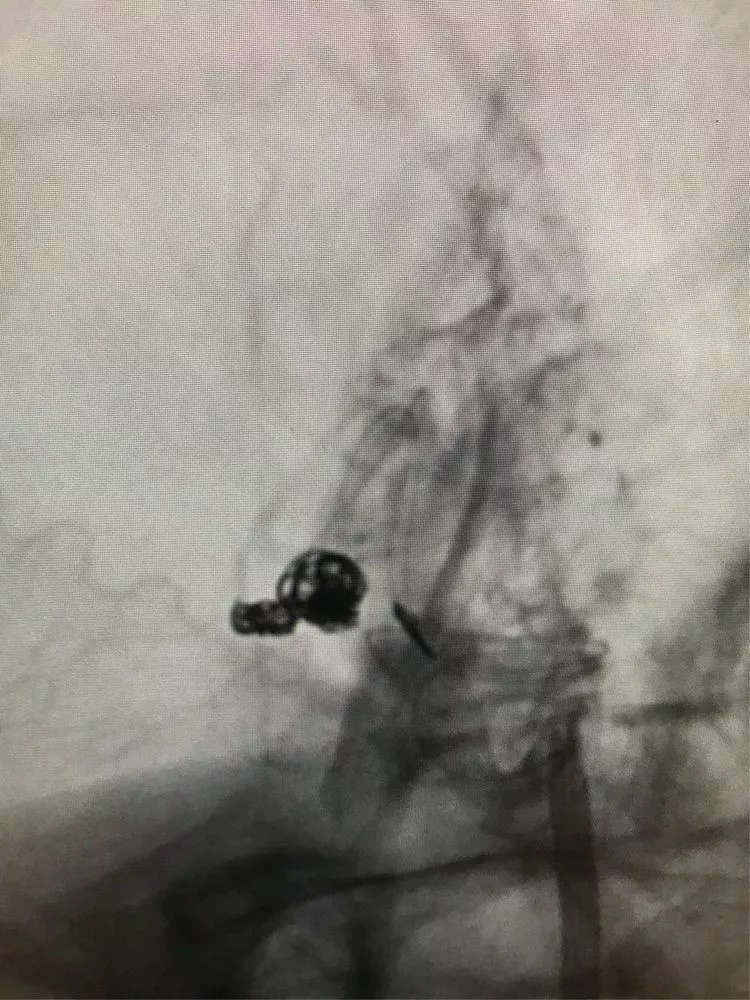

开始填主瘤。

换了一个角度进行填塞,主要是观察前交通的部位,避免弹簧圈影响到前交通。第一个成篮圈最为关键,既要避免分隔,又要保证不影响前交通。

然后双导管交替填塞,小心啊!每填完一个弹簧圈都造影看双侧大脑前A2的血流通畅情况。